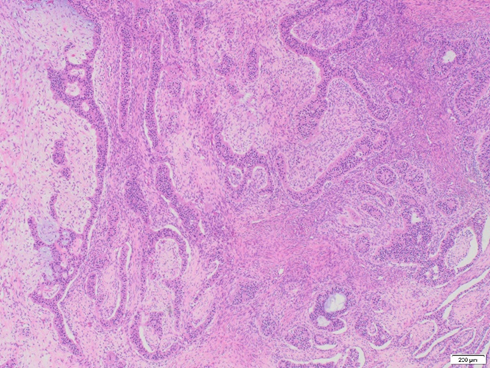

A 60-year-old woman presents with urinary symptoms, abdominal distension and bloating. A CT scan shows a large pelvic mass. A bilateral salpingo-oophorectomy with omentectomy is performed and reveals a 27.5 x 22.5 x 17.9 cm white, firm, and solid mass in the left ovary. Immunohistochemical staining shows positivity with pan-cytokeratin, CAM5.2, ER, PR, WT1, and PAX8 (patchy). Beta-catenin shows nuclear patchy staining. Calretinin, inhibin, and SF-1 are negative in neoplastic cells. The neoplastic cells are negative for GATA3, TTF-1, CDX2, INSM1, chromogranin, and synaptophysin.

Endometrioid carcinomas are morphologically heterogeneous, with a spectrum of appearances similar to those seen in endometrioid carcinomas of the uterus, potentially constituting a diagnostic pitfall (Malpica, 2016). On rare occasions, endometrioid carcinoma mimics sex cord-stromal tumors, a common scenario encountered in the ovary. These tumors can form solid or hollow tubules, nests, and elongated cords, such as in our case.

The distinction between endometrioid carcinoma with a sex cord pattern and a true sex cord-stromal tumor is based on recognizing this unconventional architecture and confirmation with immunohistochemical stains. The tumor is frequently positive for EMA and cytokeratins and negative for sex cord markers. Although PAX8 may be often negative, ER, PR, beta-catenin, and CD10 has been expressed most studies (Travaglino et al., 2024). Despite its unusual morphology, endometrioid carcinoma with a sex cord pattern typically behaves as a low-grade tumor and shows an excellent prognosis when confined to the ovary (Young et al., 1982).